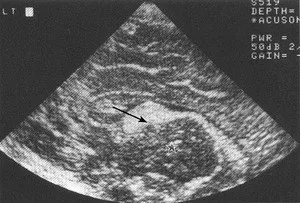

Jeżeli krwawienie zlokalizowane jest tylko w macierzy rozrodczej to według obowiązującej klasyfikacji w modyfikacji Papilla, jest to krwawienie I stopnia. (ryc. 1). Gdy krew przedostanie się do światła komór bocznych mózgu, w zależności od ich wypełnienia, mówimy o krwawieniu II stopnia (10-20% objętości komór) (ryc. 2) lub krwawieniu III stopnia (powyżej 50% objętości komór bocznych). (ryc.3). Najcięższą postacią krwawienia do OUN jest krwawienie do okołokomorowego miąższu mózgu i nazywane jest zawałem żylnym krwotocznym przykomorowym.

Ryc .2 Krwawienie II stopnia